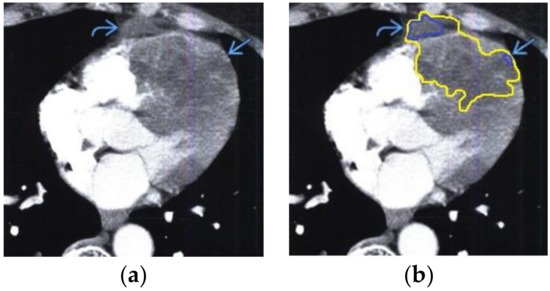

The contour extraction method was used to identify cancerous areas that, after applying the model to eliminate mixed noise, had an increased contrast of volumetric heterogeneous formations in the region of the heart [27]. This method was developed by the authors when analyzing thermal images to assess the condition of the coronary vessels of the myocardium under cardiopulmonary bypass. The contours of the cancerous regions in the examples used for applying the model to eliminate mixed noise (Figure 4, Figure 5, Figure 6, Figure 7, Figure 8 and Figure 9) are highlighted in yellow and they represent the visual boundary of the distribution of volumetric heterogeneous formations.

• For a patient with heart and pericardial lymphoma: during MRI with contrast enhancement, the volumetric formation of a heterogeneous structure in the right atrium and thickened pericardium was determined (Figure 8).

Figure 8. Heart MRI: (a) image with white noise and (b) denoised image with contrast enhancement of lymphoma in the right atrium.

Applsci 10 04747 g008